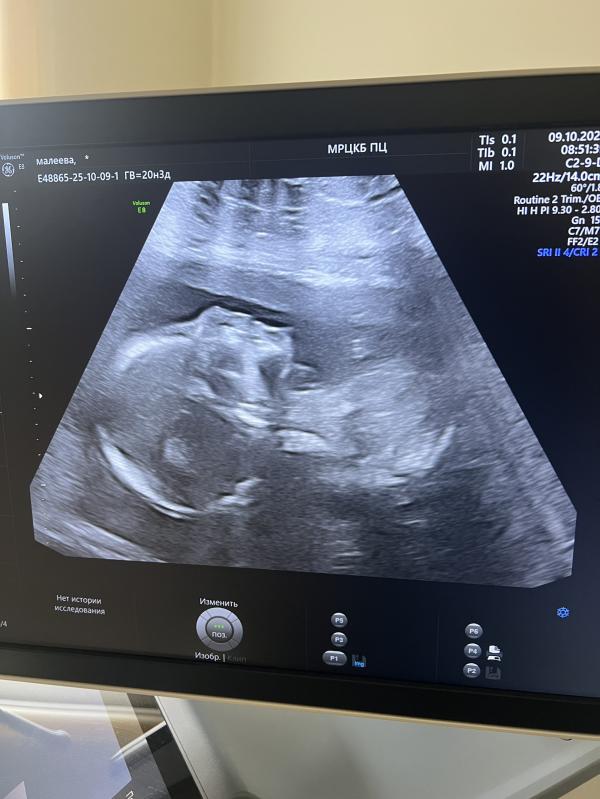

По результатам НиПта , но сегодня был скрининг 2-й и я еще раз убедилась что она самая моя 3-я доченька 🌸

Лапочка дочка💞